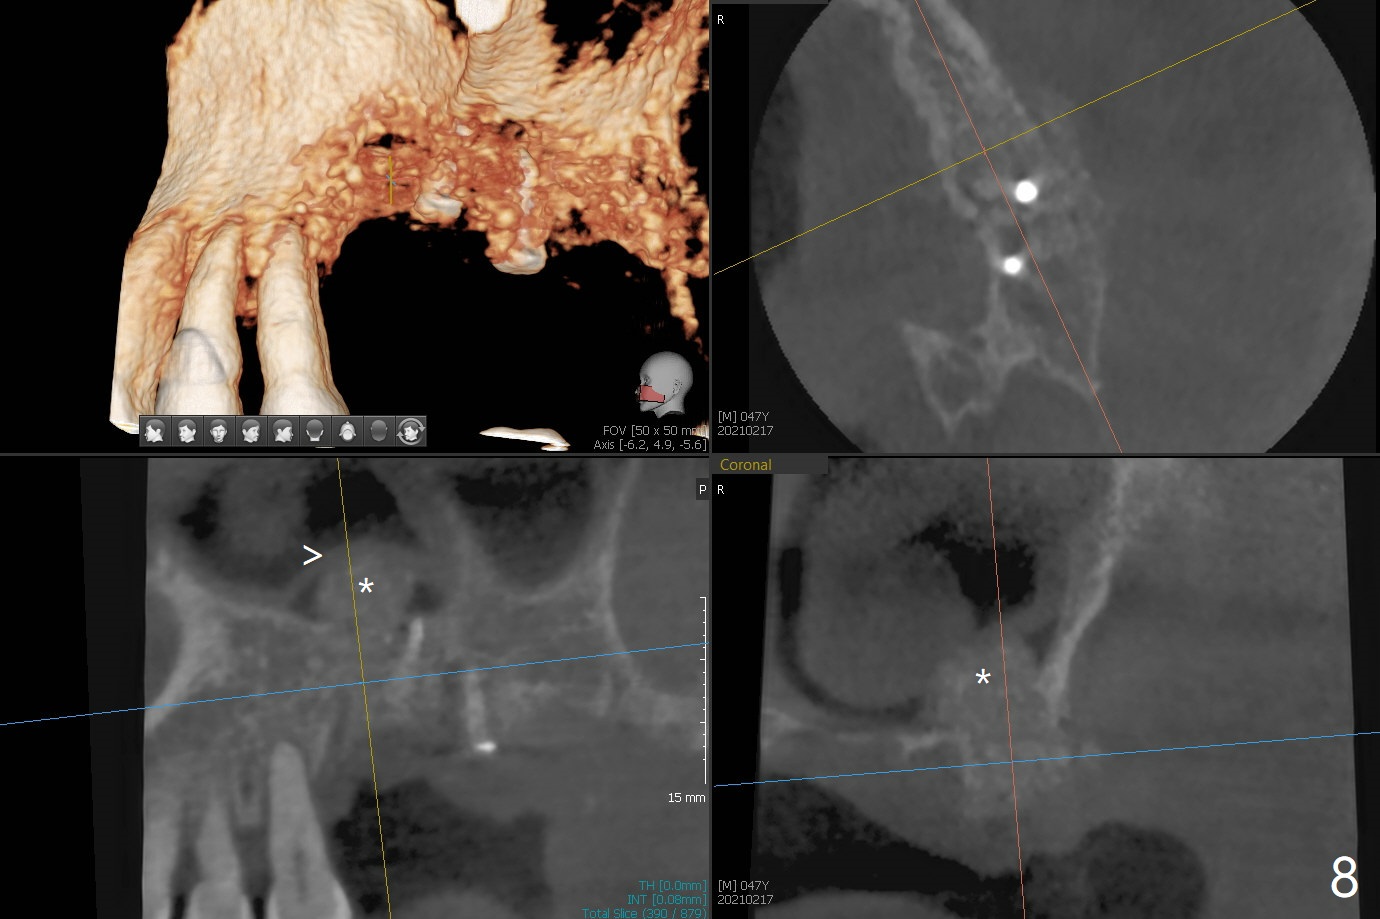

47岁男原本回诊所拔除近中左上智齿(16号牙),影响第一磨牙(14号牙)植牙周围炎治疗后卫生维护。事先制备PRF(图一,二)和骨块(图三 *),拔牙顺利,发现植牙螺纹依然暴露,决定取出植体,上颌窦底板缺失,但膜仿佛完整,放置一小块PRF于上颌窦底,促进上颌窦膜愈合,然后加入新的骨粉,与剩余上清液(图三 >)调袢,虽然不再形成粘性骨块,但是还有好处,放置于拔牙窝以及植牙窝(图四 *),浅部放置骨块(S),这样骨粉不容易丢失,表面再放置PRF膜和不可吸收膜(Cytoplast),使用PTFE缝线。术后7周Cytoplast几乎完全暴露(图五)。当它取出后,骨粉好像损失不少(图六)。二个月后再评价。术后6.5月第一磨牙区仍萎缩(图七),只好再植骨,在第三磨牙区安置一个tenting screw,也在第一磨牙区植入第二个钉子,但是不牢靠,因为仍处于纤维状,把它往上颌窦推作为上颌窦粘膜(图八:>),然后提升(*)。在第一,第三磨牙交界处打入第二个帐篷钉,在两个钉子周围放置粘性骨粉,覆盖PRF膜,缝合。估计植骨效果不佳,植牙时再植骨。